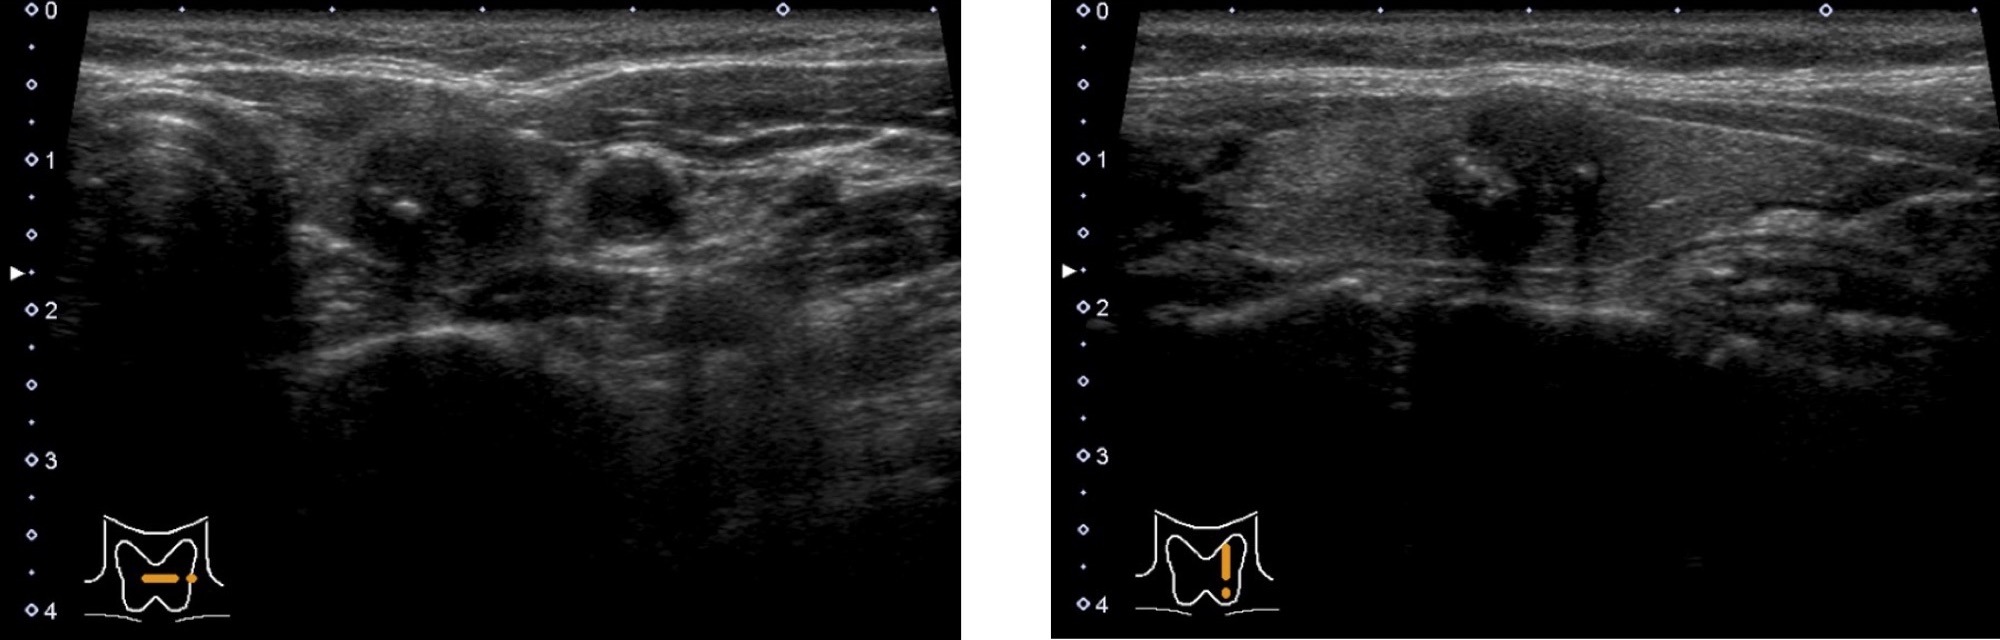

乳頭がん

形はいびつ(形状不整)で、甲状腺との境界がはっきりしていません(境界不明瞭)。

内部は黒っぽく(内部エコーレベル低)、点状の白い部分(微細高エコー)があります。

内部は充実性(固体)のことが多いです。

乳頭がんのリンパ節転移

乳頭がんは首のリンパ節(頸部リンパ節)に転移を起こすことが多いです。

正常なリンパ節と比べて、腫れて大きくなったり、白っぽくなったり(エコーレベル上昇)、点状の白い部分が見えたり(微細高エコー)、嚢胞成分(液体)を伴ったりします。

リンパ節転移の有無や部位によって手術術式が異なりますので、手術前に超音波検査でリンパ節を確認することは重要です。